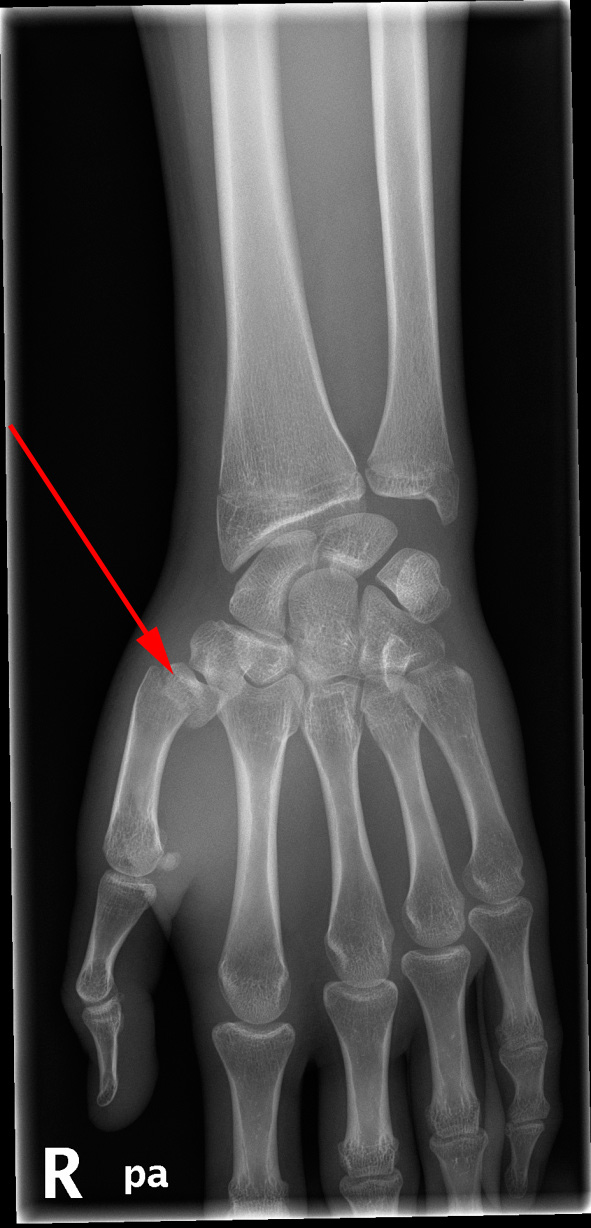

Røntgenundersøgelse af højre hånd viser en fraktur i tommelen (rød pil) - en såkaldt Bennetts fraktur.